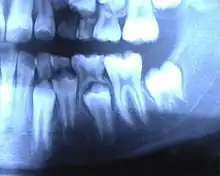

Molaire de lait en place, avec la prémolaire visible dessous.

• Racines : plus fines et plus divergentes, laissant place au germe sous-jacent de la dent permanente.